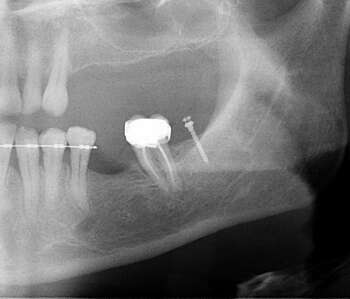

Cas 1 : Redressement d'une molaire mésioversée